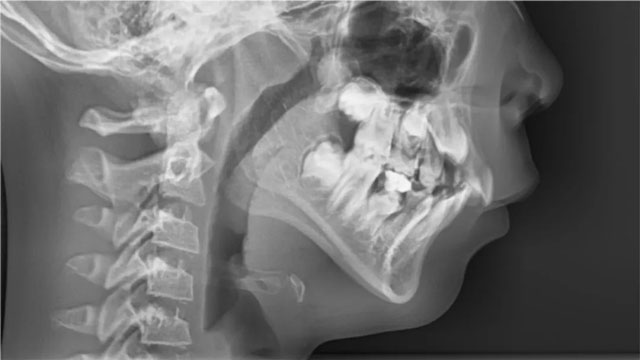

這次就診和以往有所不同,除了拍片和檢查,關醫生還仔細查看了他們夫妻的面型,告訴他們診斷結果是:中重度深覆蓋、深覆合,輕度下巴后縮。

隨后,關醫生分析了原因:“牙齒和面型問題受遺傳因素影響很大,孩子應該是遺傳了爸爸。先天因素加上長期的口呼吸,造成了現在這個情況。”從未關注過自己下巴的彤彤爸爸照了下鏡子,有點尷尬。媽媽補充說彤彤奶奶也有這個問題,有嚴重的齙牙,嘴很突。

關禹哲醫生:彤彤換牙偏晚偏慢,門牙牙根還沒發育好,如果做矯形,治療周期會很長,加力不合適會影響到牙根發育;從她的年齡和口頜系統發育階段來看,今后做功能矯形的時間還很充裕。所以,對她來說當下就佩戴功能矯治器不是必須的,且弊大于利。彤彤正處于下頜骨發育高峰期,經過半年的肌功能訓練,深覆蓋、深覆合和下巴后縮都得到了明顯改善,達到了治療目的。當然,彤彤的情況只是個例。

關禹哲醫生:彤彤這樣的情況屬于II類錯頜畸形,上頜下頜都存在一些問題。上頜不僅有深覆蓋、深覆合,還有上牙前突。她目前正處于生長發育中,牙弓形態還會變化,可能因為遺傳因素的影響變得更加前突,今后可能需要通過拔牙內收牙弓。如果現在就導下頜向前,很可能造成雙頜前突,目前這個方案對她來說是最優的選擇,后期會根據生長發育情況考慮是否需要用功能矯治器進行擴弓等治療。

關禹哲醫生:下巴后縮屬于II類錯頜畸形,原則上提倡早期干預,但早期干預也需要滿足一定的條件,包括牙根發育是否完成,能否移動,后縮是否嚴重,年齡因素等。如果不能滿足以上條件,可能涉及過早、過度治療,治療后可能出現反彈的情況。